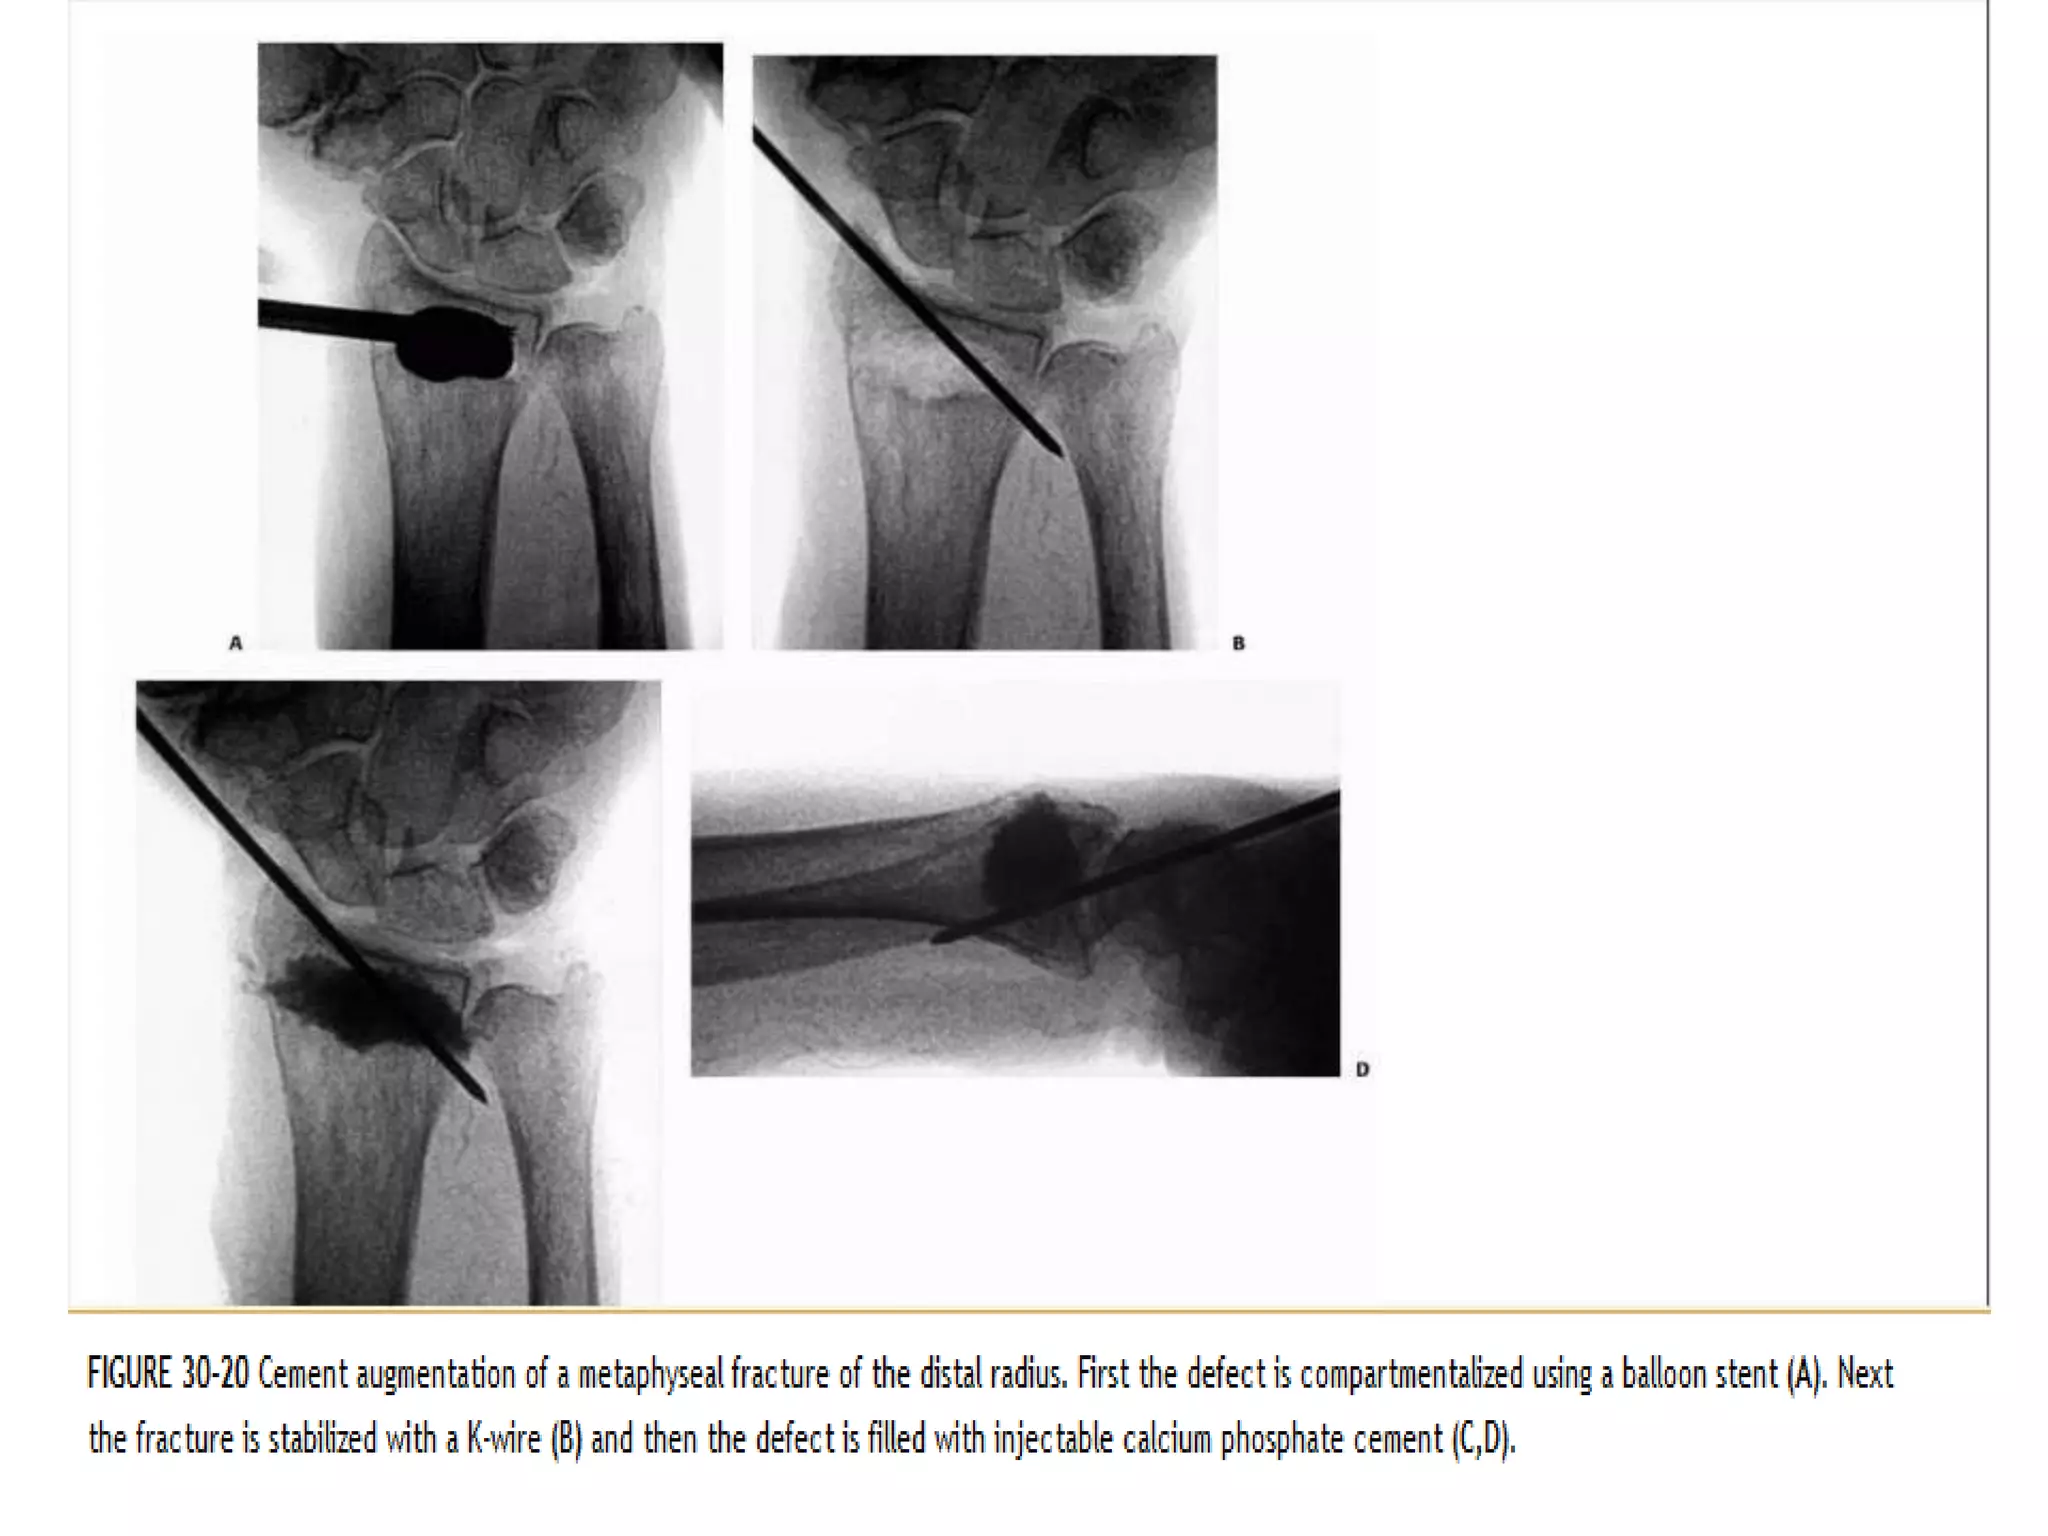

Both bone inductive and conductive, which have been

proposed to fill the metaphysis and prevent fracture

collapse.percutaneous introduction of a calciumphosphate

bone cement to treatment with external fixation or cast

application. The radiographic results demonstrated

superior maintenance of radial length in the cement

group.